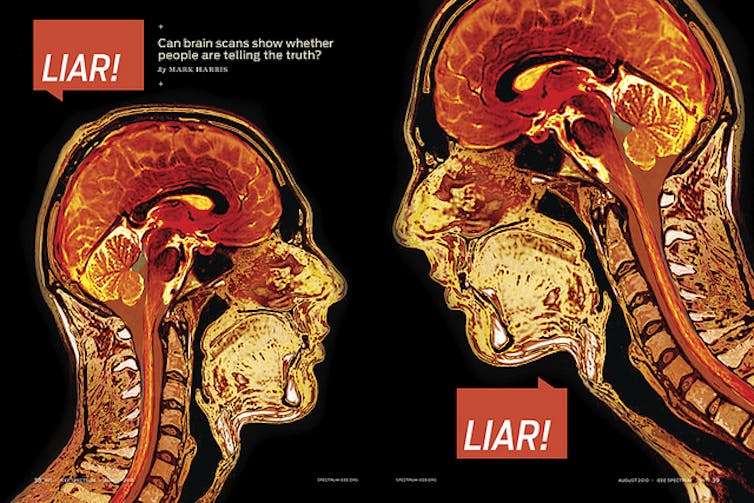

Thousands of papers have subsequently been published, all with images of blobs on brains.

All sorts of mental phenomena are now routinely scanned, from viewing simple shapes to emotional states, such as disgust, religious belief, love and beyond, to psychosis, depression and psychopathy.

We love the blobs and have become accustomed to them. No matter what the quality of the message, if it’s accompanied by images of brain blobs and explained with some neurobabble, we are ready to believe it.

The blobs, we are told, and believe, signify activity that explains the mind. But they actually do no such thing.